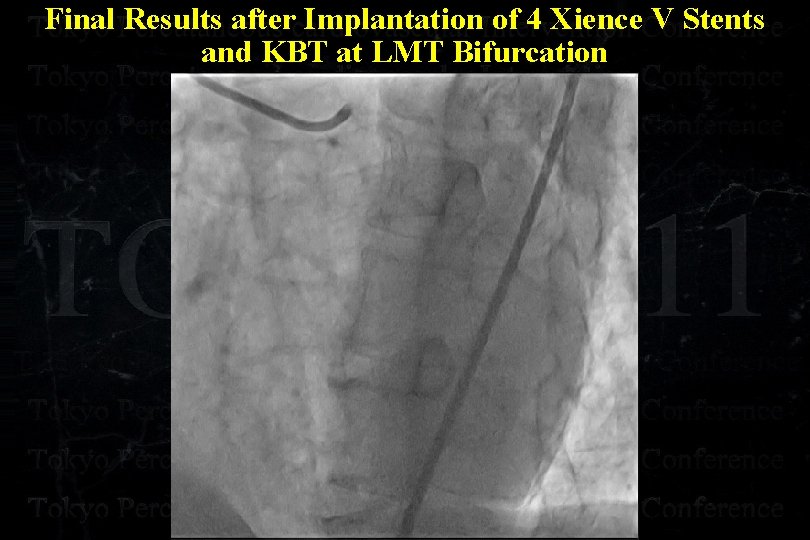

Final Results after Implantation of 4 Xience V Stents and KBT at LMT Bifurcation

Final Results after Implantation of 4 Xience V Stents and KBT at LMT Bifurcation

Final Results after Implantation of 4 Xience V Stents and KBT at LMT Bifurcation